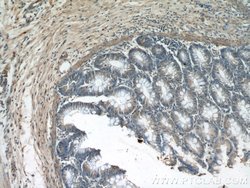

GULP1 Rabbit anti-Human, Mouse, Rat, Polyclonal, Proteintech

The prompt clearance of cells undergoing apoptosis is critical during embryonic development, normal tissue turnover, inflammation, and autoimmunity. CED6 is an evolutionarily conserved adaptor protein required for efficient engulfment of apoptotic cells by phagocytes.Specifications

Immunohistochemistry (Paraffin), Western Blot | |